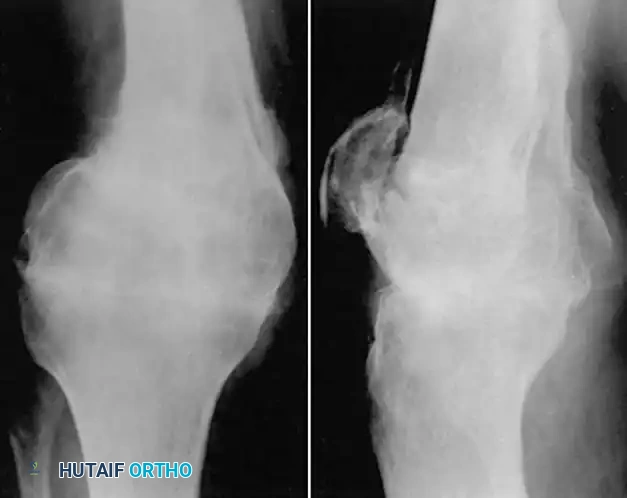

FIGURE 58-23 A: Distal femoral fracture presenting with a severe 30-degree varus malunion.

Image

FIGURE 58-23 B: Application of a circular external fixator to gradually correct the deformity and restore length prior to definitive internal fixation.

FIGURE 58-23 C: Final radiographic appearance after external fixator removal, corrective osteotomy, and rigid plate osteosynthesis.

FIGURE 58-21: Radiograph 3.5 months after compression arthrodesis for a severe distal femoral malunion with articular collapse. The knee is stable and painless.